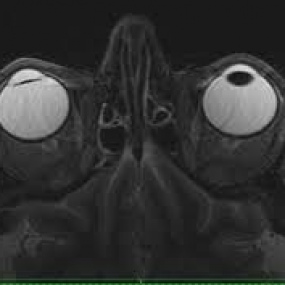

Resonancia nuclear magnetica de orbitas simple y contrastada. EN. Codigo CUPS 883103 SC (2022)

ESCANOGRAFIA NEUROLOGICA S.A.

Medellin, Barrio Prado Centro: Calle 59 # 50 A - 14

Sabaneta, Carrera 48 # 50 sur 128. Al interior del Centro Comercial Mayorca Mega Plaza